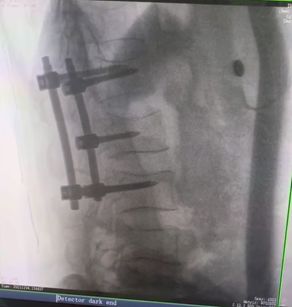

骨科C臂機 三維C形臂助力手術更準確產品說明:

三維C形臂,也叫術中CT,它可以術中采集三維圖像,生成類CT斷層圖像及橫斷面圖像,為手術診斷提供多角度信息,有效輔助術中植入物定位以及置入結果檢查。主要適用于骨科、脊柱外科、矯形外科、創(chuàng)傷骨科等科室,尤其適用于復雜部位的外科手術。那么,三維C形臂與二維C臂相比,能夠給臨床帶來哪些優(yōu)勢呢?

例如治療先天性脊柱側后凸畸形,由于脊柱自身復雜的解剖結構限制,使得脊柱外科手術對于準確度有著較高要求。以往我們只能采用傳統的正側位圖像來判斷螺釘置入的位置,現在三維C形臂特有的類CT斷層成像,使得治療過程可視化,立體化,在術中非常直觀地判斷螺釘植入的準確度。可有效引導術者植入后路螺釘并切除半錐體。同時可以在術中實時驗證手術效果。有效地縮短了手術時間,降低手術風險,避免了不必要的術后翻修手術。